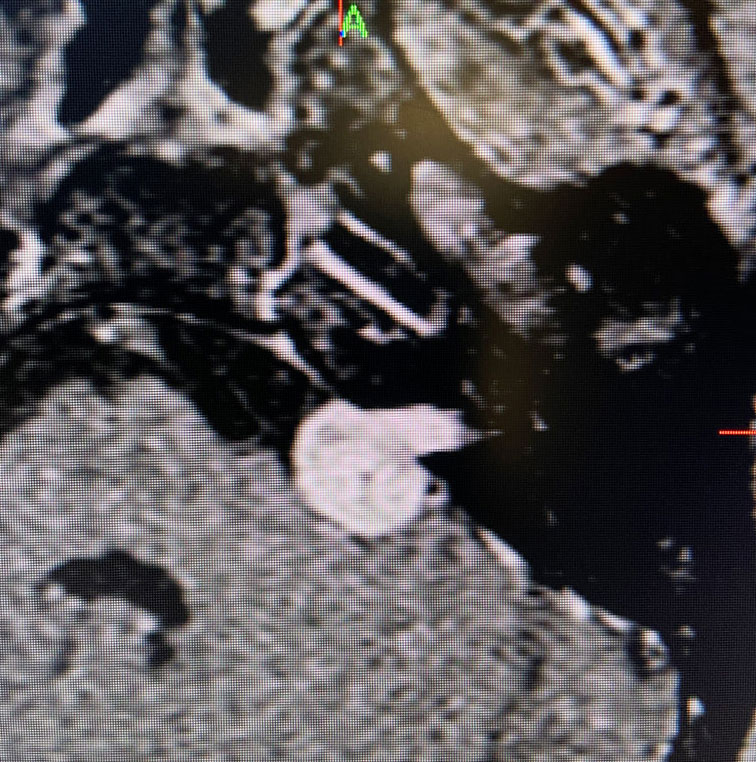

Image 1: Pre-operative imaging of the left acoustic neuroma.

This is a 55 year old woman with a history of hypertension who sought attention because of one year of progressive hearing loss in the left ear. The hearing in that ear was now about 50% of normal. She also had ringing in the left ear (tinnitus). She had no problems with her right ear. Her balance was normal and she had no other complaints. Formal audiology testing confirmed hearing loss in the left ear only. MRI with and without gadolinium demonstrated a 1.3 cm solid mass in the left cerebello-pontine angle and internal auditory canal that showed homogeneous enhancement, consistent with an acoustic neuroma.